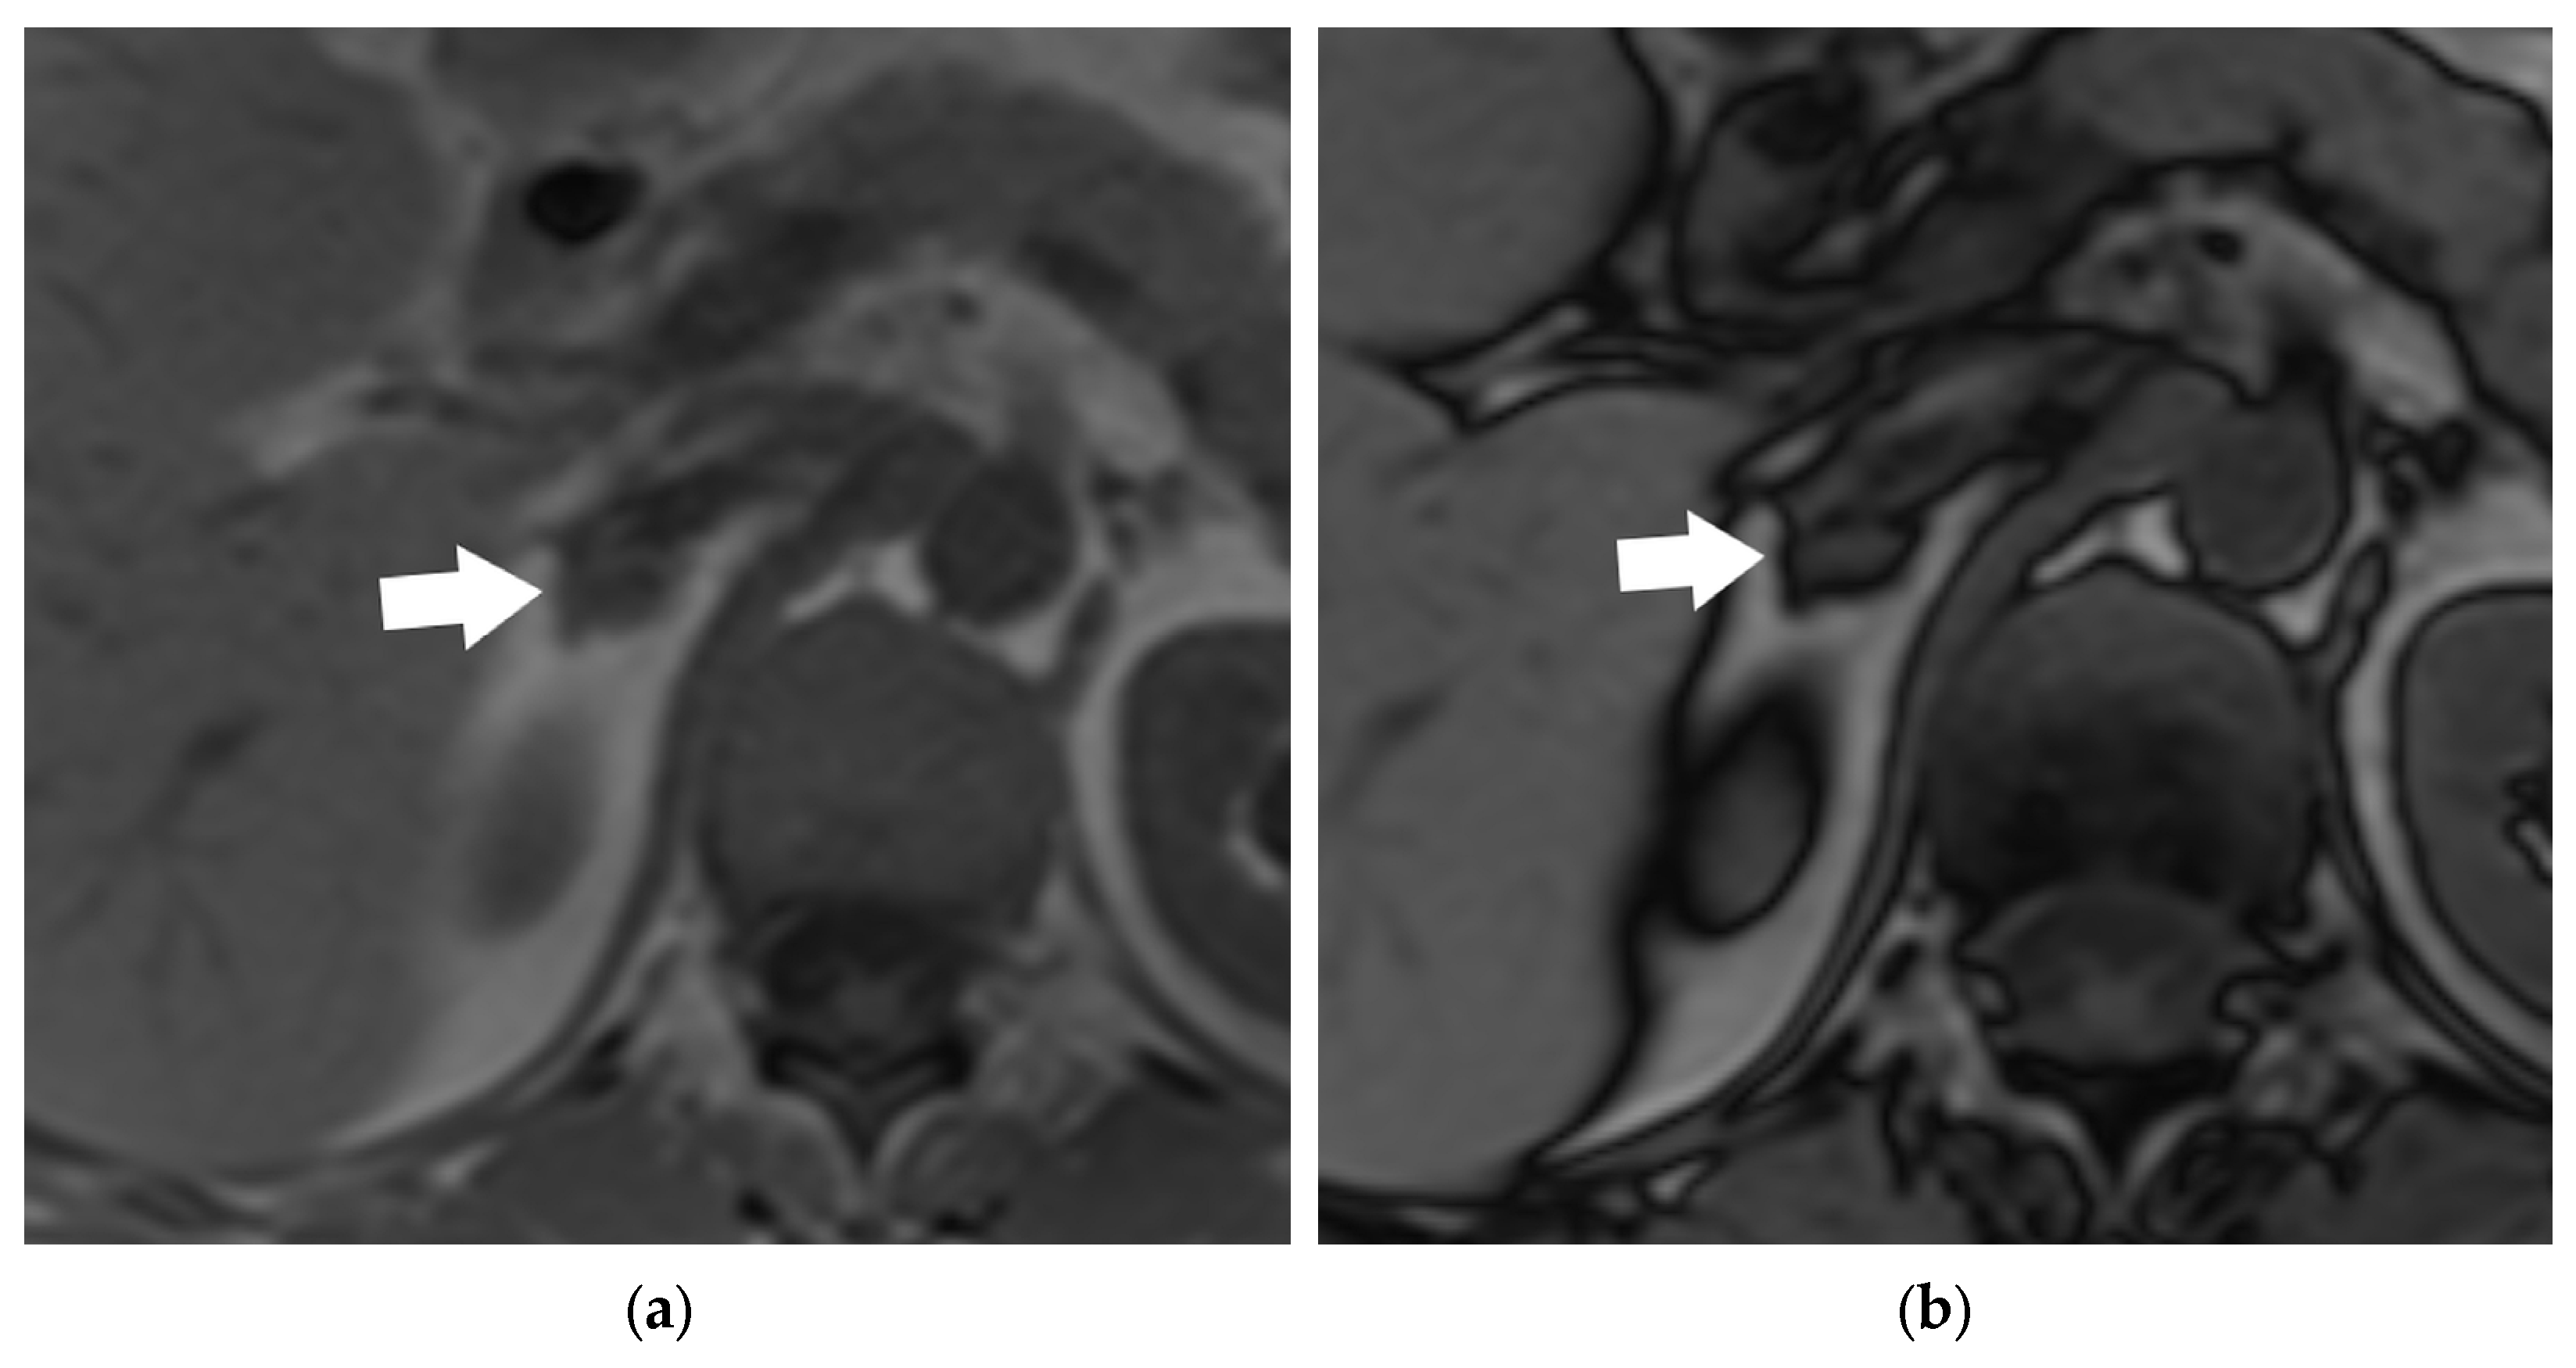

- Schieda, N.; Siegelman, E.S. Update on CT and MRI of Adrenal Nodules. Am. J. Roentgenol. 2017, 208, 1206–1217. [Google Scholar] [CrossRef]

- Metser, U.; Miller, E.; Lerman, H.; Lievshitz, G.; Avital, S.; Even-Sapir, E. 18F-FDG PET/CT in the evaluation of adrenal masses. J. Nucl. Med. 2006, 47, 32–37. [Google Scholar] [PubMed]

- Martin, S.S.; Weidinger, S.; Czwikla, R.; Kaltenbach, B.; Albrecht, M.H.; Lenga, L.; Vogl, T.J.; Wichmann, J.L. Iodine and Fat Quantification for Differentiation of Adrenal Gland Adenomas From Metastases Using Third-Generation Dual-Source Dual-Energy Computed Tomography. Investig. Radiol. 2018, 53, 173–178. [Google Scholar] [CrossRef]

- Albano, D.; Agnello, F.; Midiri, F.; Pecoraro, G.; Bruno, A.; Alongi, P.; Toia, P.; Di Buono, G.; Agrusa, A.; Sconfienza, L.M.; et al. Imaging features of adrenal masses. Insights Imaging 2019, 10, 1. [Google Scholar] [CrossRef] [PubMed]